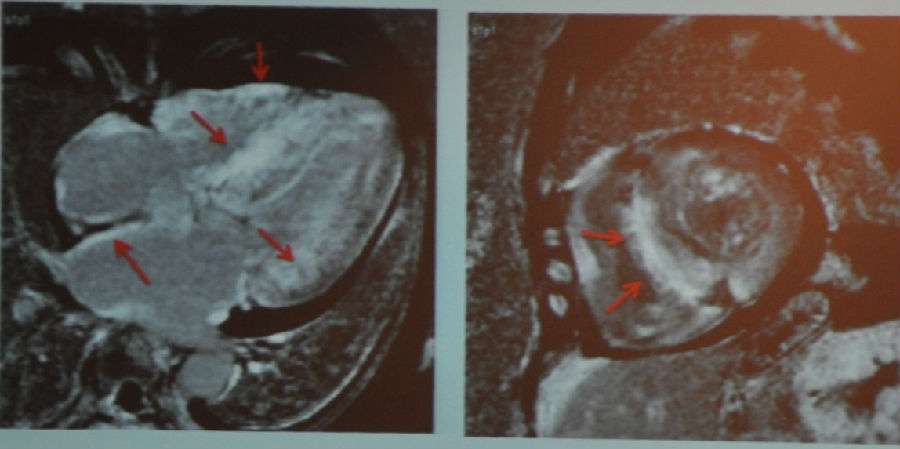

图2 MR电影成像

室间隔壁变薄,心尖部收缩功能不全,短轴观示前壁收缩功能不全。心尖部有异物。

图3 MR增强成像(从左到右依次为三腔心切面、四腔心切面、短轴切面)

从MR增强成像中可以看到,心脏上黑色的部分是正常心肌,而白色的部分为瘢痕组织。该图显示了心肌梗死的典型表现。通过增强我们可以看到心尖部的异物是一个血栓,这个在一般的心脏超声上是难以发现的,因为它非常小。我们还可以看到,实际上患者心梗的面积要比上面短轴观所示前壁收缩功能不全的程度严重得多。

那么这名患者的诊断就非常明确了,是缺血性心肌病。他很快被送往导管室行PCI治疗。3个月后患者再次来院行磁共振检查,其心脏收缩功能获得了显著的改善。